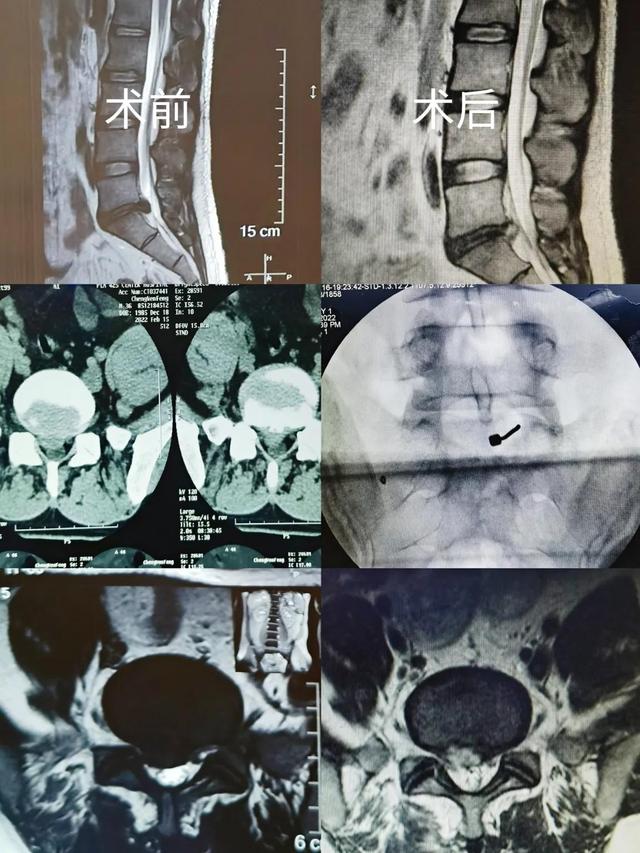

椎间孔镜手术(腰椎间盘突出症患者的福音)

腰椎间盘突出症是指腰椎间盘发生退行性病变后,纤维环部分或全部破裂,髓核单独或者连同纤维环、软骨终板向外突出,刺激或压迫窦椎神经和神经根引起的以腰腿痛为主要症状的一种综合征。对于需要手术治疗的腰椎间盘突出症患者。椎间盘...